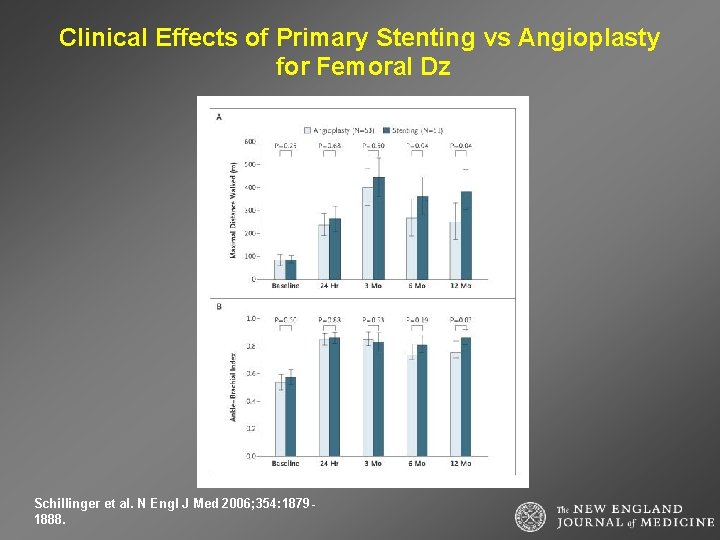

Angioplasty vs. Stent in the Superficial Femoral Artery Schillinger, M. et al. N Engl J Med 2006; 354: 1879 -1888

Clinical Effects of Primary Stenting vs Angioplasty for Femoral Dz Schillinger et al. N Engl J Med 2006; 354: 18791888.